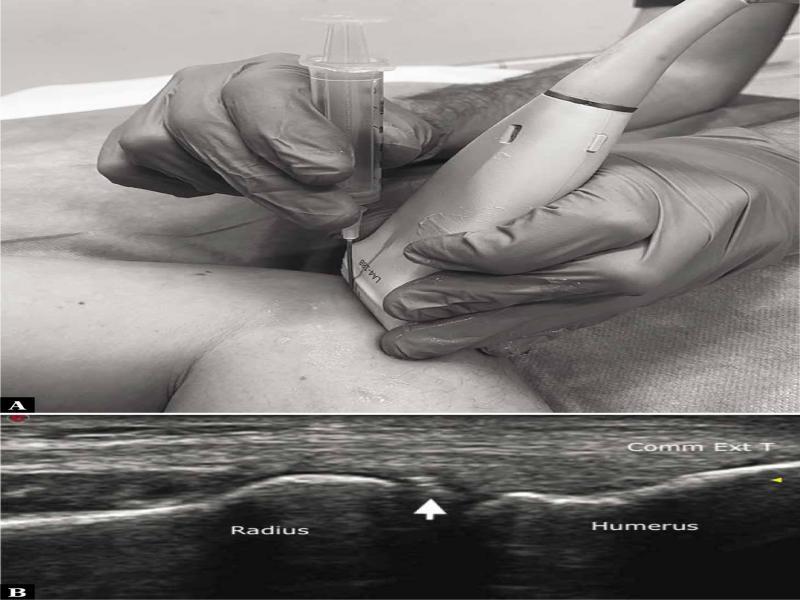

Fig. 1.